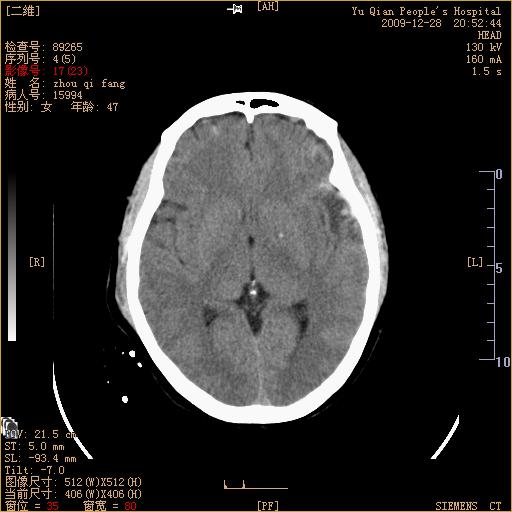

头部外伤后1天   请看看左侧丘脑外侧原是否为小血肿?(两天表现大致相仿。)谢谢

左颞叶前外部见片状挫裂伤,左丘脑小血肿;颅板下见多发小片状血肿影,两侧额部见少量蛛网膜下腔出血,

左额叶颅内板下也有一高密度灶。。。考虑多发小灶性出血(挫裂伤)。。。复查后再定

不好定。同时左侧裂池形态异常,左侧豆状核点状高密度,第四幅右额叶稍高密度影,最后一幅左额叶颅骨内板下方小片状高密度影。复查。